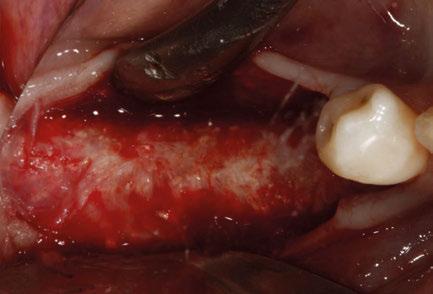

maxilectomía parcial que incluyó las piezas 24-26 y desde el reborde alveolar hasta la base del cráneo (Figuras 3 y 4). En este caso, la órbita y el globo ocular pudieron ser preservados. La reconstrucción inmediata se realizó mediante un colgajo de músculo temporal homolateral (Figura 5) y el defecto de la fosa temporal fue cubierto mediante una malla de titanio. Posteriormente, la paciente recibió radioterapia (Figuras 6 y 7). 2 años más tarde se diseñó un IS con anclaje en el arbotante nasomaxilar, zona subnasal izquierda

y lo que se pudo preservar del hueso malar. Se añadió una malla sinterizada infraorbitaria para dar volumen a la mejilla y se planificaron dos brazos de conexión que emergieran en las posiciones 24 y 26 de forma subgingival (Figuras 8 y 9). La superficie interna que apoyaba en el hueso era de titanio microrrugoso, y la superficie externa y conectores de titanio pulido y hexágono externo universal (Figuras 10 y 11). La cirugía se hizo bajo anestesia general en infiltración con anestesia local (4% articaína, 1:100.00 epinefrina), levantando el

colgajo cutáneo de la mejilla por vía intraoral, preservando el colgajo temporal para no comunicar con el remanente de la cavidad naso maxilar (Figura 12). Se emplearon 10 tornillos de osteosíntesis de 1,9 mm y la estabilidad primaria obtenida fue excelente (Figura 13)